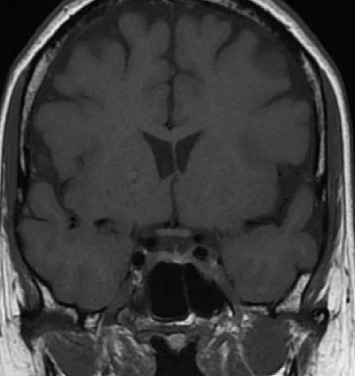

Granulomatous mastitis (GM) is a rare inflammatory condition of the breast that can mimic inflammatory breast cancer. We report a case of a 54-year-old female who developed recurrent GM symptoms in the context of drug-induced hyperprolactinemia, which resolved with dopamine agonist therapy. Our report suggests that serum prolactin should be tested in patients with GM and appropriately managed if elevated.

Abstract Image